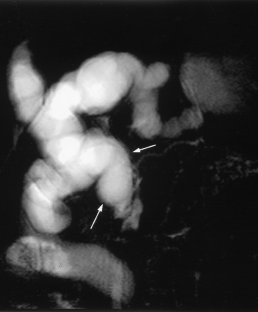

Cholestasis may result from hepatocellular (intrahepatic) disease or biliary tract (extrahepatic) abnormalities. Etiologies causing extrahepatic cholestasis are extremely diverse and invasive procedures, such as endoscopic retrograde cholangiopancreatography (ERCP) and percutaneous transhepatic cholangiography (PTC), were previously required to establish the diagnosis. Due to refinements of magnetic resonance imaging (MRI) techniques, the patient with extrahepatic cholestasis currently can be evaluated noninvasively, and the information revealed frequently exceeds the findings obtained by ERCP and PTC. In this essay, we illustrate the classic MR cholangiographic (MRC) and MRI features of a variety of disorders causing extrahepatic cholestasis, including non-neoplastic disorders of the biliary tract (congenital abnormalities, infectious processes, iatrogenic disorders, and postsurgical complications) and neoplastic conditions (e.g., tumors of the pancreas, biliary tree, liver, ampulla, and regional lymph nodes). In most cases, familiarity with the key MRC features in addition to information obtained via cross-sectional MR images provide sufficient information for adequate lesion characterization.